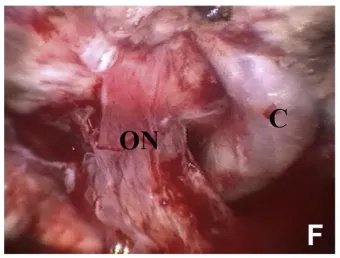

▼(F)左侧视神经(ON)向颈动脉(C)外侧移位,并因肿瘤压迫导致神经变薄。

▼(D)肿瘤(T)外侧的右视神经(ON)。

这台手术由INC国际神经外科医生集团旗下国际神经外科顾问团的德国Henry W.S.Schroeder教授亲自操刀,Schroeder教授作为德国以及国际神经内镜专家,在国际神经外科学界享有盛名。他经常作为特邀讲师指导国内神经外科专家开展垂体瘤、脑膜瘤等神经内镜手术技术培训,普及神经内镜手术在国内的应用,与国内神经外科专家共同交流进步。Schroeder教授还和德国其他教授一起合著、编纂了《神经内镜手术》一书。在神经内镜设备领域出名的小儿神经内镜Lotta内镜就是Schroeder教授在2004年发明。